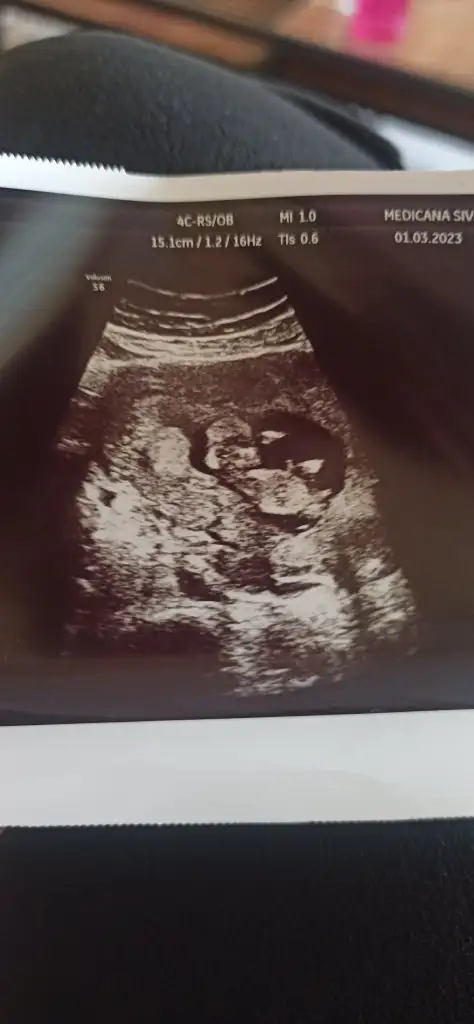

Maşallah diyelim öncelikle içimden kız geçtiKizlar 13+1 deyim bana da cinsiyet tahmininde bulunurmusunuz

Eki Görüntüle 3214911 Eki Görüntüle 3214912